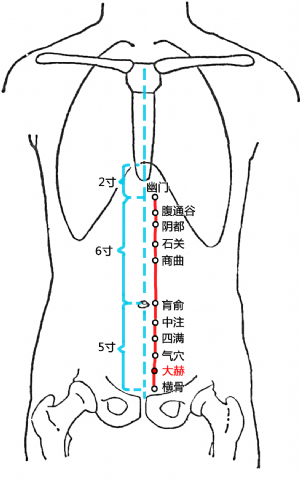

標準定位:大赫穴在下腹部,當臍中下4寸,前正中線旁開0.5寸[6]。

大赫穴位於下腹部,臍中下4寸,前正中線旁開0.5寸[6]。仰臥取穴[6]。

大赫穴位於腹正中線臍下4寸,旁開0.5寸處(《銅人腧穴鍼灸圖經》)[6]。

另說在臍下3.5寸,旁開0.5寸(《鍼灸甲乙經》);臍下4寸,旁開1寸(《鍼灸大成》);臍下4寸,旁開1.5寸(《鍼灸資生經》)[6]。

大赫穴在下腹的位置

大赫穴在下腹的位置

大赫穴位於下腹部,臍中下4寸,前正中線旁開0.5寸[6]。仰臥取穴[6]。

仰臥位,當恥骨聯合上緣中點上1寸,前正中線旁開0.5寸處取穴[7]。